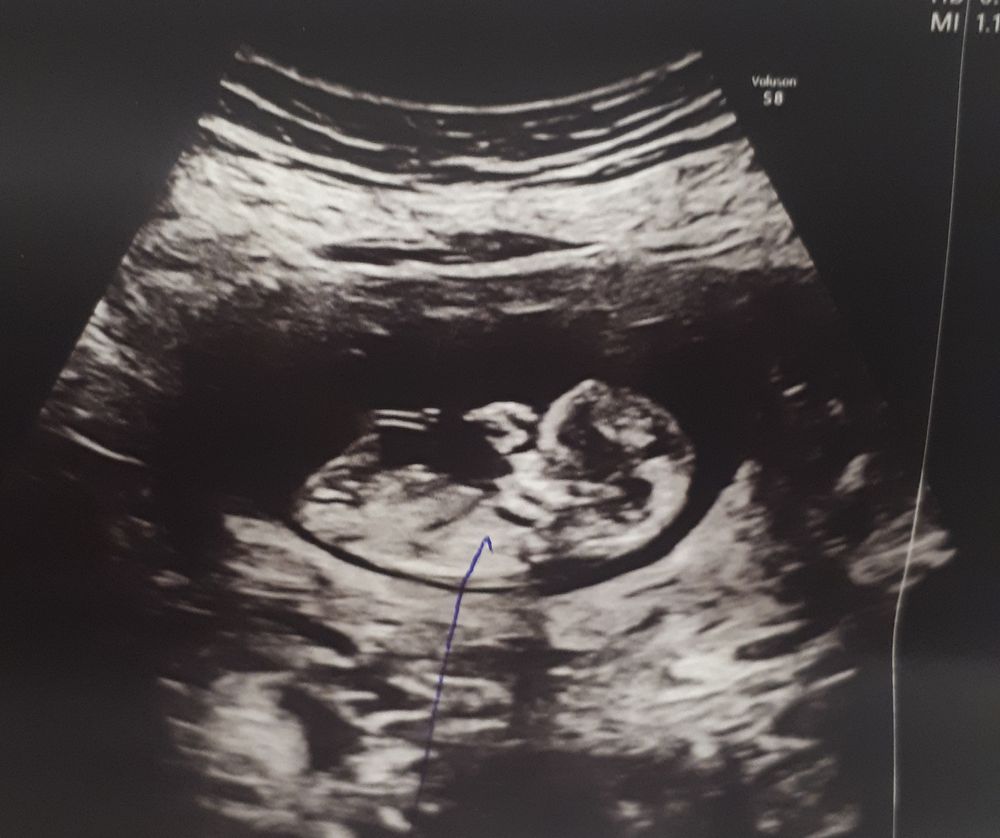

Давайте поугадываем, пока анализ на пол не пришёл)))

Как думаете? Мальчик или девочка?

Первое фото в 12 недель, а второе - в 15, видимо наша маленькая жопка 🤣🤣🤣 Полагаю узист хотел этим что-то показать🤣

Belka, ну яички выглядят по-другому. А 70% дали,что мальчик? Ну вот по этому снимку явная девочка🤷а когда анализ на кровь будет готов?